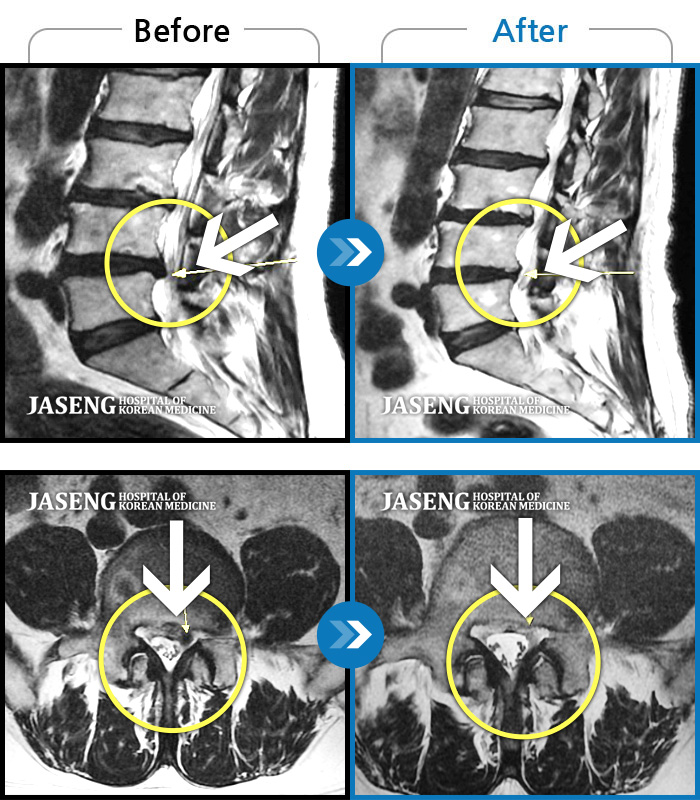

허리디스크

울산 · 정운석 원장

양측 하요추부 통증과 우측 하지 저림

촬영시기

2022.03.16 ~ 2022.11.12

2023.01.19